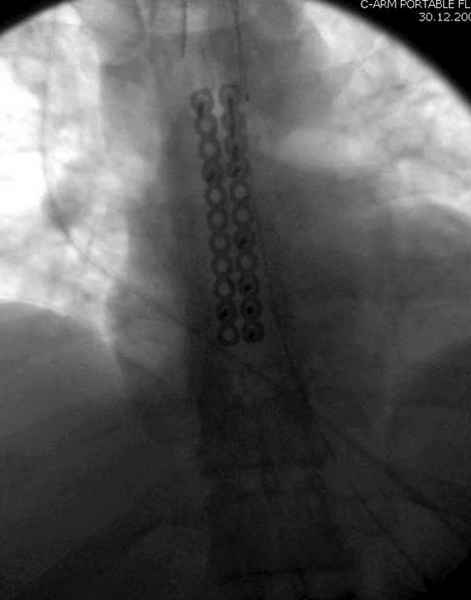

А простые посттравматические ложные суставы грудины приходилось

оперировать с ограничителем сверла и с фиксацией 2.4 мм пластинами с

угловой стабильностью.